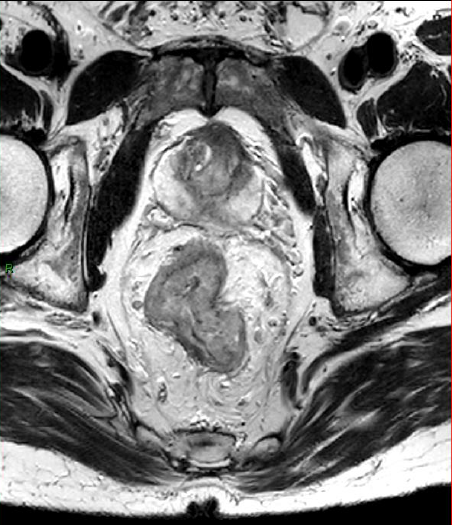

Le cancer du rectum